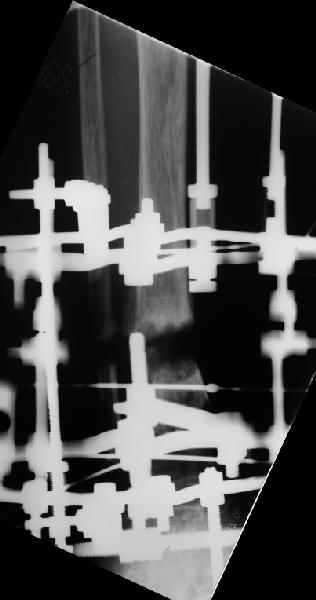

Аппарат - чтобы плавно исправить ось. В приложении - снимки на момент окончания коррекции в аппарате, фото с операции, и послеоперационная рентгенограмма.

Диаметр гвоздика 10,5 мм. Пришлось укорачивать до 23 см - уж очень миниатюрная дама, отверстия насверлил под 45 градусов, под 5 мм винты. По оси удалось сблизить до этого положения. Заперли гвоздь пока статически с планом через 2 месяца верхний винт убрать. Но это ей придется уже в Ташкенте сделать. Что скажете? Спасибо.

In attachment - x-rays at the end of alignment, the surgery, and result. The nail was cut to 23 cm. Four 45 degree holes were pre-drilled at the distal nail tip. The nail was locked statically

after some impaction. Dynamization is considered in 8 weeks. Any comments/critics?